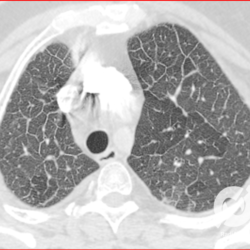

Opacidades em vidro fosco difusas com espessamento liso de septos e moderado derrame pleural bilateral.

Opacidades em vidro fosco difusas com espessamento liso de septos e pequeno derrame pleural bilateral.

Opacidades em vidro fosco, espessamento septal liso, proeminência de estruturas venosas e derrame pleural bilateral.